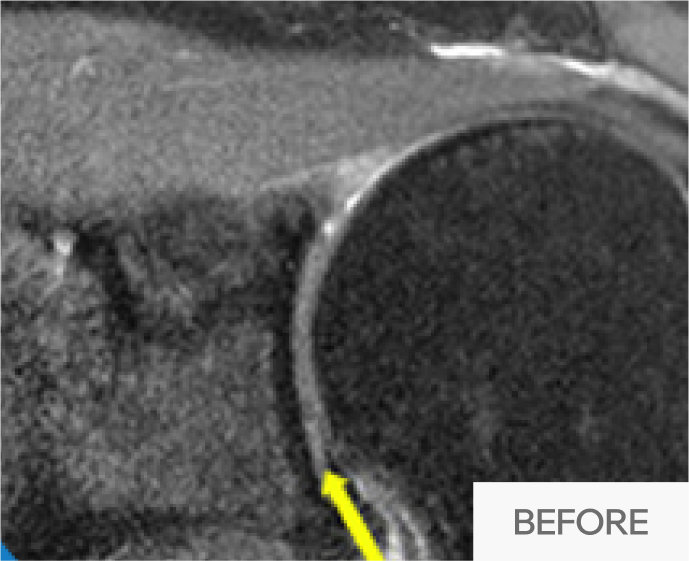

수술 상처 없이 간단한 시술로 관절막을 열어줍니다.

마취 후 전문 의료진이

어깨를 6방향으로

움직여 유착 해소

5~20분 소요

무절개, 빠른 회복

시술 중, 시술 후

빠른 통증 경감과

운동 범위 회복